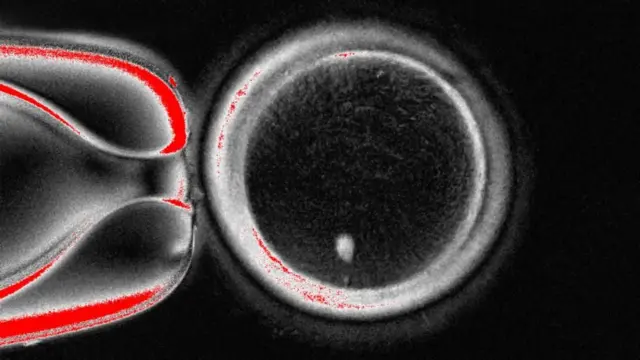

دا څېړنه، چې د (نیچر کمیونیکیشنز) په ژورنال کې خپره شوې. ښيي، چې ۸۲ فعالې هګۍ جوړې شوې دي.

دا له سپرم سره القاح شوې دي او ځینو یې د جنین د ودې تر لومړیو پړاونو پرمختګ کړی دی.

هېڅ یوه یې له شپږ ورځو هاخوا پړاو کې نه ده.